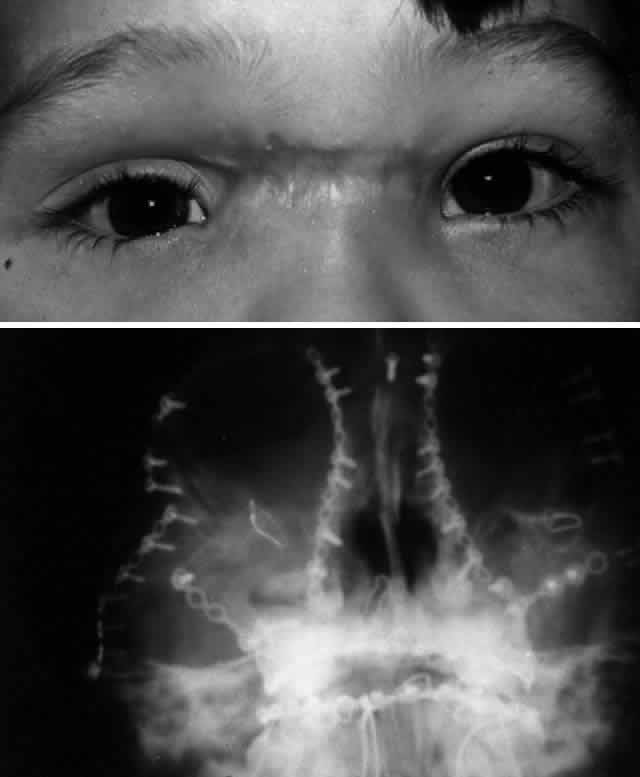

MEDIAL ORBITAL RIM (NASOETHMOID-ORBITAL REGION). The bones of the medial orbital rim represent the lateral aspect of the nasoethmoid complex, and fractures of the medial orbital rim are most typically the component of a more generalized nasoethmoid orbital injury. Nasoethmoid orbital fractures may be isolated or associated with other more extensive craniofacial fractures (e.g., Le Fort II and III). Successful management of nasoethmoid orbital injury requires consideration of both the bony and soft tissue injury.38,39,45–47 The most important soft tissue structure in the nasoethmoid-orbital region is the medial canthal tendon. The medial canthal tendon has medial and posterior insertions to the anterior and posterior lacrimal crest in the anterior portion of the medial orbit.16 Disruption of the medial canthal tendon or the bony segment containing the insertion of the medial canthal tendon can result in telecanthus. Because the lacrimal drainage system is closely tied with this area, it is at risk for injury from the original trauma as well as during surgical repair.

Type 2 fractures, because of bony comminution, generally require transnasal wiring to stabilize the central fracture segment containing the medial canthal tendon and to minimize the risk of postoperative telecanthus. The canthal tendon-bearing portion of the central fragment is isolated by subperiosteal dissection, except for the area of medial canthal tendon insertion, which is not detached. Transnasal (28-gauge) wires are passed through drill holes placed superior and posterior to the lacrimal fossa (and medial canthal tendon) and on the central fragment. These wires are then passed across the nose in a trans-septal fashion. If a bilateral nasoethmoid fracture is present, the two central fragments can be linked together. With unilateral fractures, the transnasal wire extends to the intact contralateral nasal dorsal bone. All other nasal and orbital bone segments are first linked by wires and then fixed to the frontal bone and inferior orbital rim/maxillary buttress with junctional plate and screw fixation. Tightening of the transnasal wires produces central fragment reduction and creates proper intercanthal dimensions. The intercanthal soft tissue distance is rarely overcorrected, and it is more frequently undercorrected. Therefore, transnasal reduction should deliberately minimize the bony interorbital distance between the medial orbital rims to obtain a satisfactory result.

Type 3 comminuted fractures rarely avulse the medial canthal tendon; however, the central fragment is frequently too small in such fractures to utilize in reconstruction. In such cases, the medial canthal tendon is detached and transnasal reduction of the medial orbital rim segments is performed, followed by direct transnasal wiring of the medial canthal tendon itself. The medial canthal tendon may be attached to the transnasal wire with a smaller permanent monofilament or braided suture. It is important to pass the transnasal wire posterior and slightly superior to the lacrimal sac fossa in order to achieve proper eyelid-globe apposition and impart a natural appearance to the medial canthus. Care should be taken to preserve the lacrimal system during transnasal wiring; this can be facilitated by placement of lacrimal probes within the canaliculi.

Other techniques for securing the medial canthal tendon in the setting of nasoethmoid orbital fractures have been described. Shore and associates47 described repair of telecanthus using a miniplate cantilevered from the lateral aspect of the nose and directed posteriorly into the orbit to provide a stable fixation point for the medial canthal tendon. This technique is probably most applicable for cases of unilateral traumatic telecanthus, in which poor bony support for transnasal wires is suggested on preoperative CT. After fracture reduction with transnasal wiring or medial canthal tendon fixation, soft padded nasal bolsters may be placed to help minimize edema and hematoma as well as to adapt the skin to the nasal bones. Although these external bolsters play no role in the reduction or stabilization of the medial orbital rims, some authors believe they may help mold the bones of the nose and may minimize the scarring and thickening of the medial canthal tissues. These bolsters are secured with an additional transnasal wire, which is removed 7 to 10 days after surgery. Adequate aesthetic repair of extensive fractures in this region can be challenging.